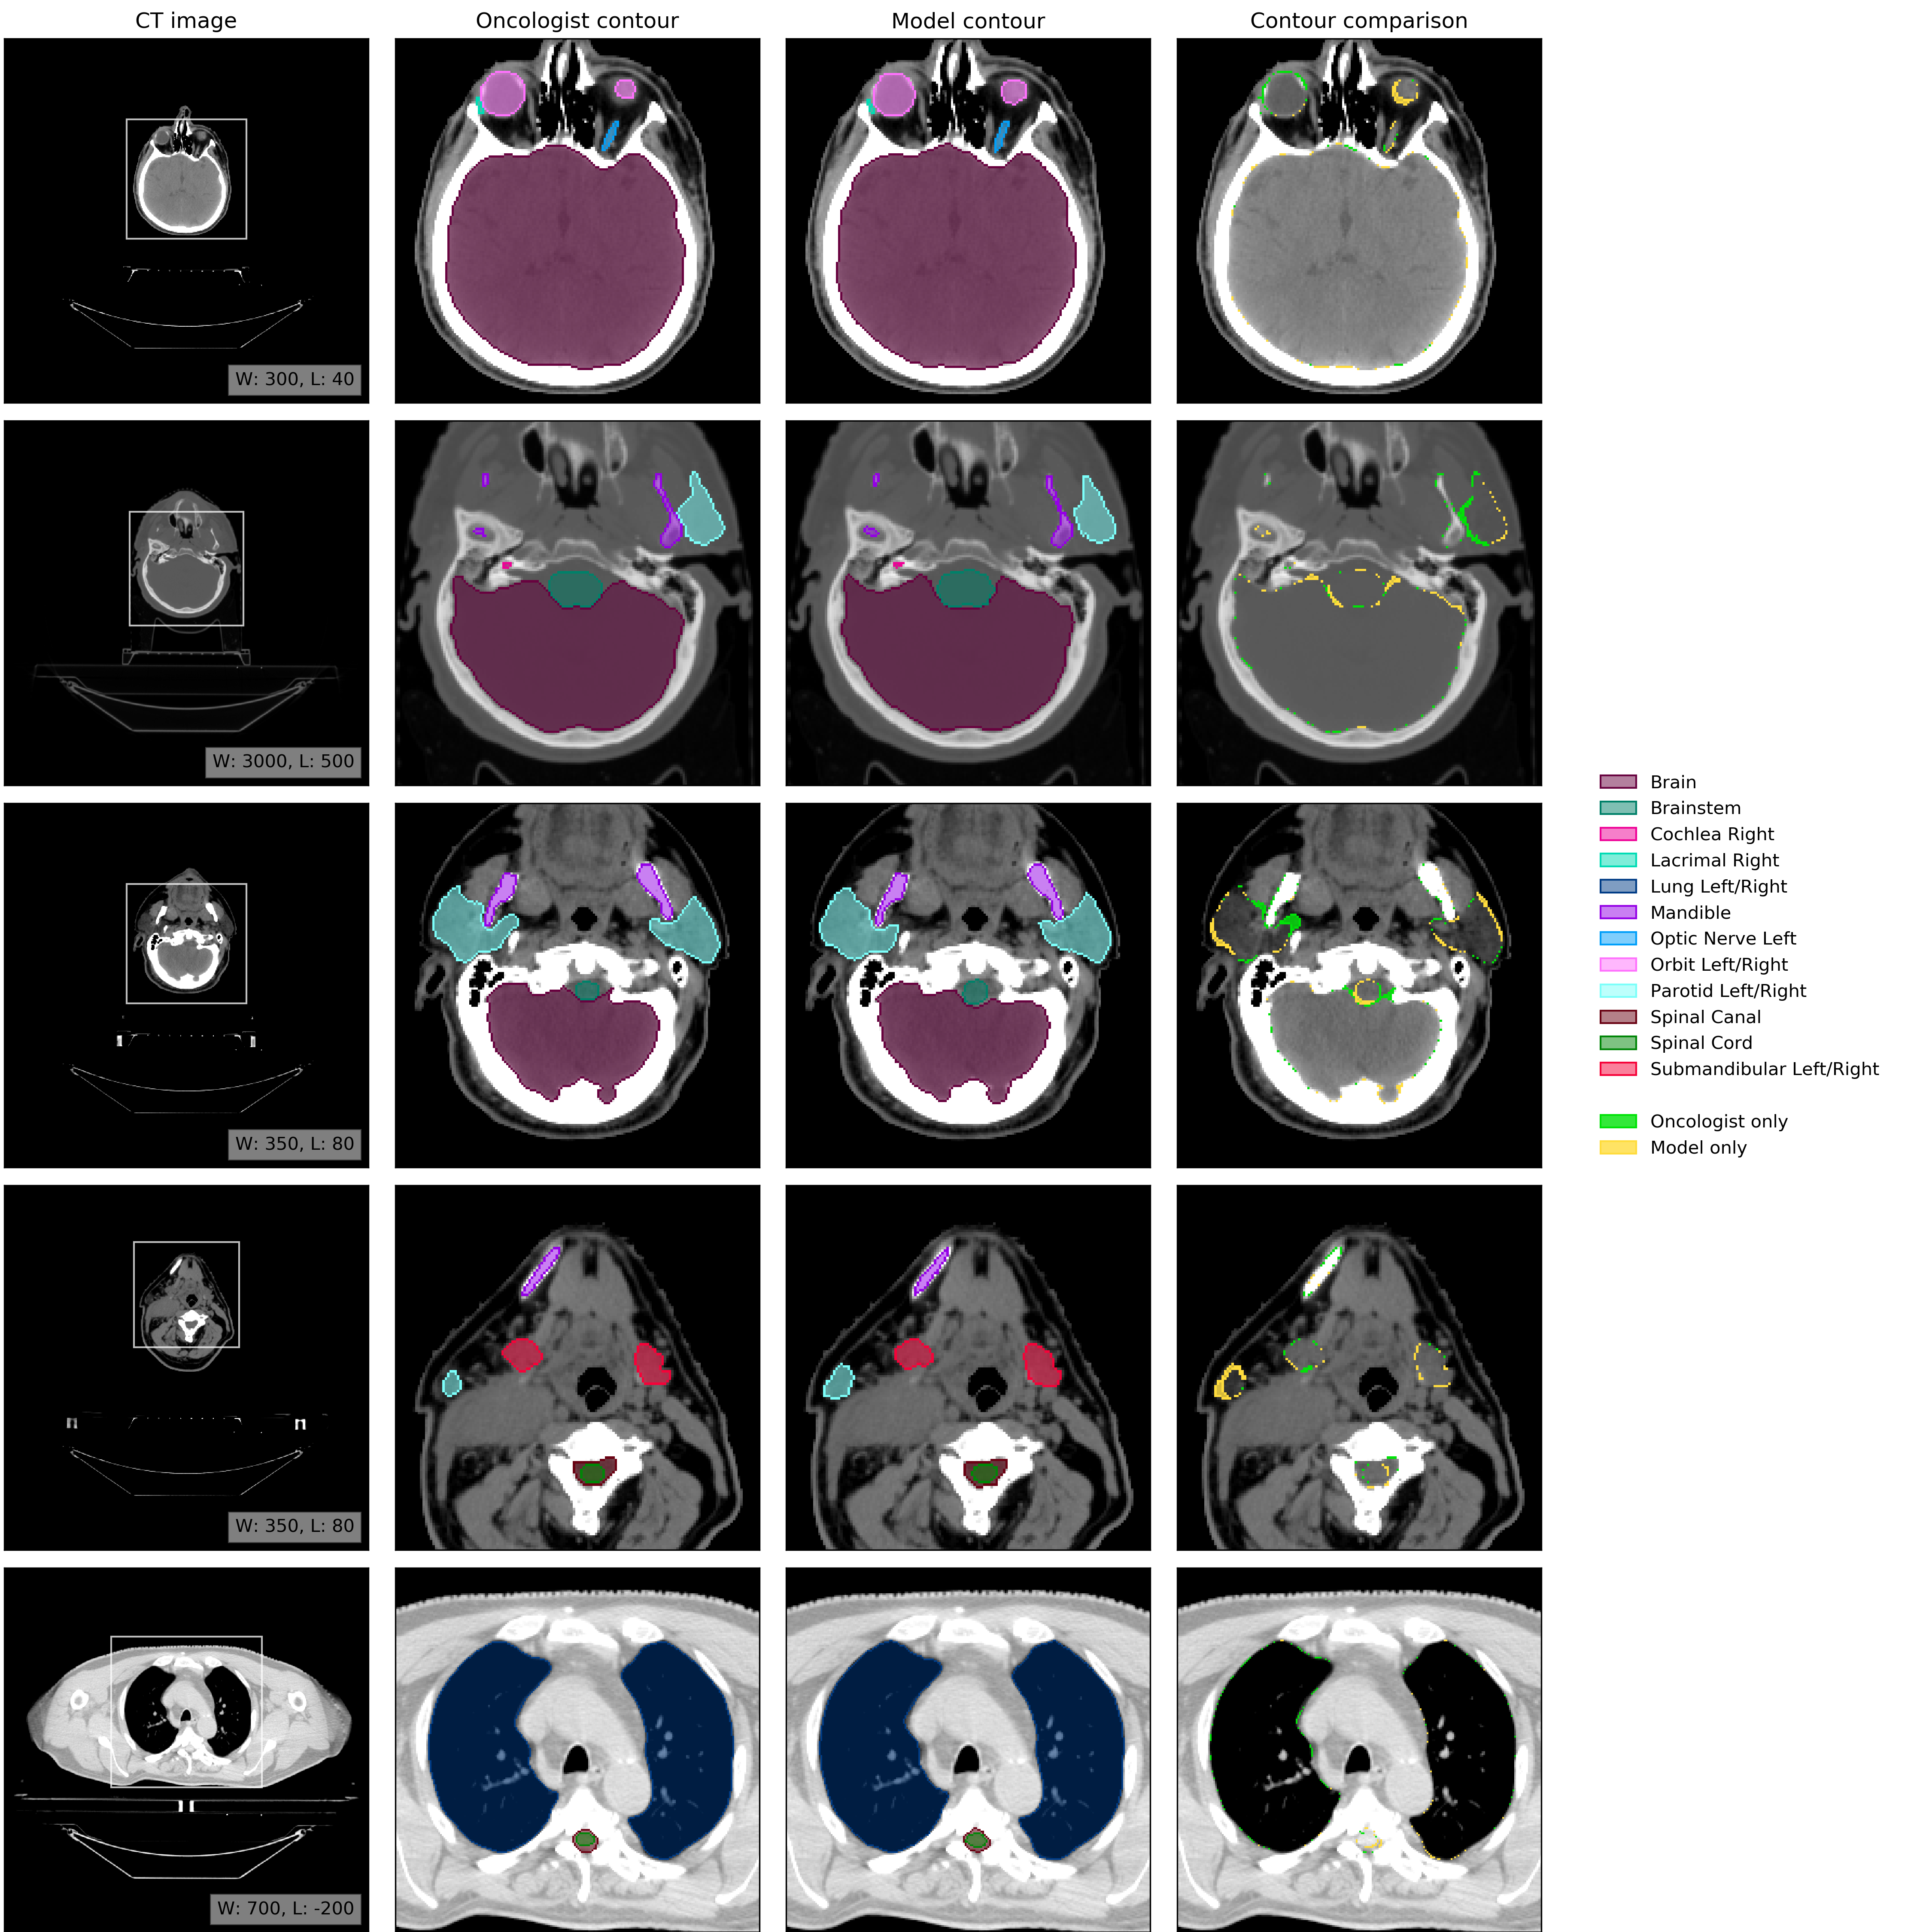

An example of model performance is shown in Fig. 2. We compare our performance (model vs oncologist) to radiographer performance (radiographer vs oncologist). For more information on dataset selection, inclusion and exclusion criteria for patients and OARs please refer to the Methods section.

Refer to caption

Figure 2: Example results. (CT image) Axial slices at five representative levels from the raw CT scan of a 55-59 year old male patient was selected from the UCLH dataset (patient UCLH-20) were selected to best demonstrate the OARs included in the work. The levels shown as 2D slices have been selected to demonstrate all 21 OARs included in this study. The window levelling has been adjusted for each to best display the anatomy present. (Oncologist contour) The ground truth segmentation, as defined by experienced radiographers and arbitrated by a head and neck specialist oncologist. (Model contour) Segmentations produced by our model. (Contour comparison) Contoured by Oncologist only (green region) or Model only (yellow region). Two further randomly selected UCLH set scans are shown in Fig. 12 and Fig. 13. Best viewed on a display.